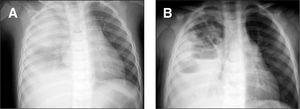

Varón de 2 años, que ingresó por fiebre de 41 °C, tos, diarrea y rechazo alimentario. Presentaba un regular estado general, 36 resp./ min, 120 lat./min, temperatura 39,8 °C, palidez y sudoración. A la auscultación existía soplo tubárico en hemitórax derecho y semiología de derrame pleural en el tercio inferior y zona paraescapular, siendo el resto normal. La analítica reveló 17.300 leucocitos/μl con desviación a la izquierda; sodio, 132 mmol/l; proteína C reactiva, 15,7 mg/dl, y dímero D > 7 μg/ml. La gasometría arterial fracción inspiratoria de oxígeno (FiO2) al 21 % mostró pH, 7,37; PO2, 31,2 torr; PCO2, 39,3 torr; HCO3, 22 mmol/l y saturación del 58 %. En la radiografía de tórax se observó una opacidad en hemitórax derecho, broncograma aéreo en lóbulo medio y lóbulo inferior derecho y condensación alveolar en lóbulo superior derecho con derrame organizado (fig. 1A). Se inició oxigenoterapia, antitérmicos, cefotaxima 200 mg/kg/24 h i.v. y vancomicina 15 mg/kg/6 h i.v. La radiografía del tercer día mostró desplazamiento mediastínico contralateral a expensas de derrame pleural e imágenes areoladas en lóbulo superior derecho, con loculación y organización, y se consultó a la UCI para inserción de tubo de drenaje. El líquido pleural presentaba aspecto purulento; pH, 7,26; 660 leucocitos/μl (95 % polimorfonucleares), glucosa, 2 mg/dl; proteínas, 3,8 g/dl, y LDH 7.090 U/l. Los cultivos, el Ziehl y Löwenstein fueron negativos, así como los hemocultivos, y la prueba de tuberculina. Tras la inserción del tubo torácico, en la radiografía se apreció derrame loculado e imagen cavitada de paredes gruesas, instilándose durante 2 días consecutivos 100.000 U de urocinasa intrapleural. A las 48 h, y habiendo drenado mínimamente, en una ecografía se apreció ausencia del tubo en la cavidad pleural, extrayéndose el mismo. Durante los 6 días siguientes continuó séptico y la radiografía mostró múltiples niveles hidroaéreos por loculaciones pleurales y cavitaciones en lóbulo superior derecho (fig. 1B). En la TC torácica (fig. 2A) se confirmó amplia destrucción con necrosis parenquimatosa en lóbulo superior derecho y colapso del lóbulo inferior derecho con sinequia pleural anterior en el seno del empiema, por lo que se colocó nuevo tubo torácico. El drenaje fue prácticamente nulo en los días siguientes. Una segunda TC torácica reveló que el tubo estaba nuevamente fuera de la cavidad pleural. En este momento (día 13 de ingreso), se consultó con neumología, y se decidió insertar un tercer tubo de drenaje, con control exhaustivo, obteniendo 475 ml de líquido purulento acompañado de burbujeo persistente con la aspiración, traduciendo la presencia de fístula broncopleural. El paciente presentó una mejoría clínica y radiológica espectacular, con reexpansión pulmonar y resolución de las lesiones cavitarias de lóbulo superior derecho. Al mes y medio del alta, la TC mostró desaparición de las cavidades, con tractos fibrosos y refuerzo pleural, y a los 8 meses ausencia de lesiones (fig. 2B).

Figura 1. A) Radiografía posteroanterior de tórax al ingreso que muestra veladura prácticamente completa del hemitórax derecho con borramiento de hemidiafragma homolateral, broncograma aéreo en lóbulo medio y lóbulo inferior derecho y zona de mayor densidad homogénea que delimita imagen redondeada en lóbulo superior derecho, lo cual sugiere la presencia de condensación alveolar con derrame pleural acompañante, parcialmente organizado.B)Múltiples puntos hidroaéreos a expensas de loculaciones pleurales, y lesiones cavitadas visibles en lóbulo superior derecho (décimo día de ingreso).